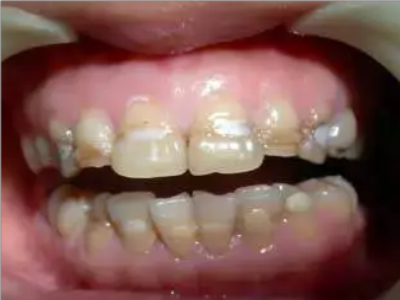

牙釉质发育不全牙齿上棕色的坑图

牙釉质发育不全程度严重时,牙齿上出现较深的条状、点状凹陷,内含深褐色物质,并且牙齿尖端的牙釉质缺失,牙齿变得相对脆弱。